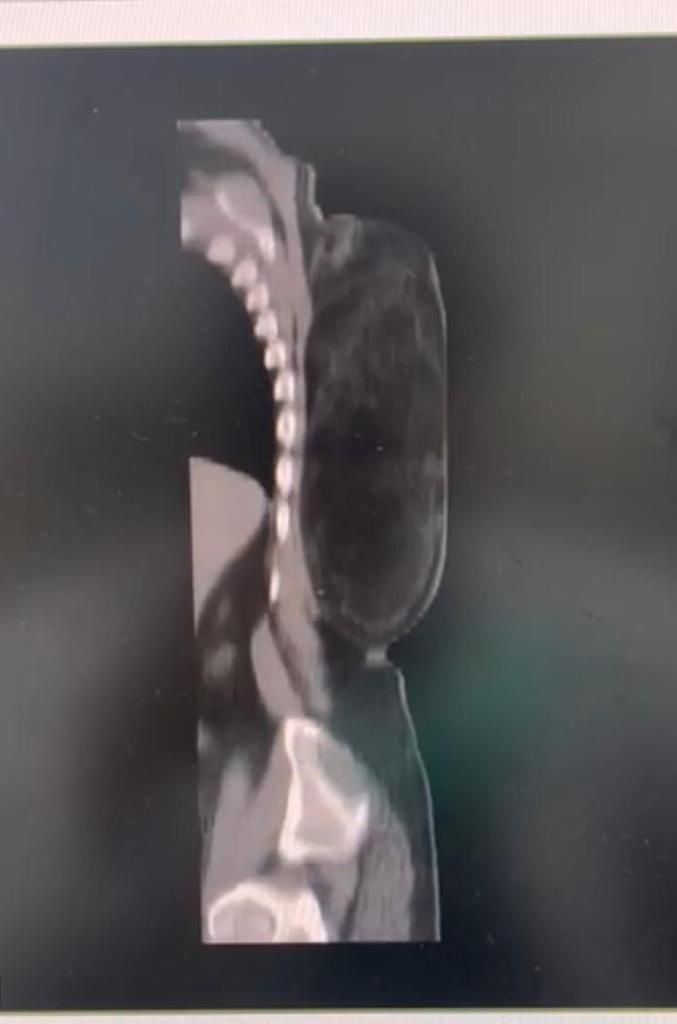

تمكن فريق طبي جراحي في مستشفى الملك فهد بجدة في إنقاذ حياة مريض في العقد السادس من العمر، وذلك بعد تمكنهم من إجراء عملية جراحية لإزالة واستئصال ورم مرتجع كبير الحجم في ظهره وممتد إلى جوار عضلات العمود الفقري.

وكان المريض الستيني قد وصل طوارىء مستشفى الملك فهد بجدة بعد مروره بظروف صعبة ومعاناة مع الكتلة الورمية الضخمة، والتي سبق أن أزالها في بدايتها بأحد المستشفيات ولم يكن كافياً، حتى انتكست حالته الصحية، وقد تم اخضاع المريض لفحوصات كاملة بعد استشارة الفريق الجراحي بالمستشفى، والذي قرر بعد مراجعة نتائح  الفحوصات ضرورة إجراء عملية جراحية عاجلة لإستئصال الورم الضخم.

وأوضح الفريق الطبي الجراحي  بالمستشفى أن حجم  الورم يبلغ ٤٠ سم في ٣٠ سم حيث يقارب وزنه ثلاثة كيلو، وأشاروا أيضاً أن المريض كان يعاني من هذا التورم الضخم من فترة طويلة و لا يستطيع ممارسة  نشاطه اليومي و النوم على ظهره لمدة ثلاث سنوات، مبينين أن المريض الآن وبعد إجراء العملية الجراحية له و إزالة الورم بدأ يتماثل للشفاء وبصحة جيدة، وسوف يحتاج المريض لإستكمال باقي العلاجات الطبية المقررة له بعد العملية للإستشفاء